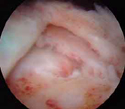

επιχειλίος χόνδρος μετά απο την αποκατάσταση (0.25MB)

Βλάβη Bankart πριν και μετά απο την αποκατάσταση